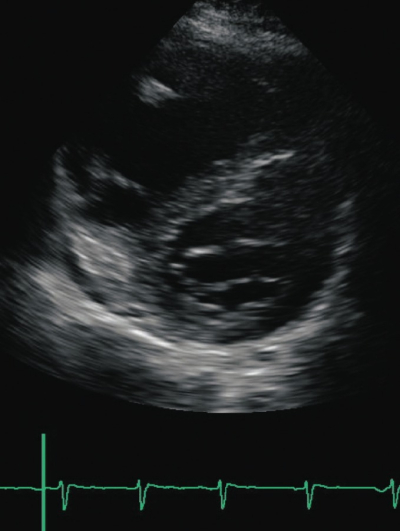

身長 155 cm、体重 80 kg。体温 36.2 ℃。脈拍 76/分、整。血圧 130/60 mmHg。呼吸数 24/分。SpO2 90 %(room air)。胸部の聴診でⅡ音の亢進を認める。両下肢に著明な浮腫を認める。神経学的所見に異常を認めない。12誘導心電図と心エコー図とを別に示す。

この患者の病態の原因として考えられるのはどれか。3つ選べ。

a. 膠原病

b. 急性右室梗塞

c. 僧帽弁閉鎖不全

d. 特発性肺動脈性肺高血圧症

e. 慢性肺血栓塞栓性肺高血圧症